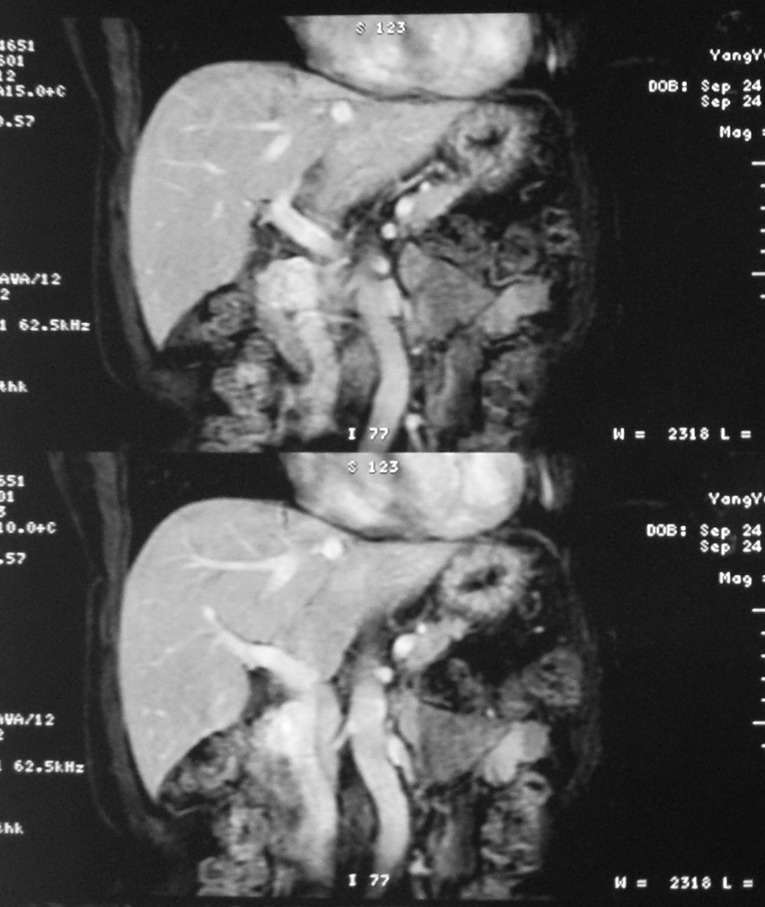

标题: MRI2066:腹膜后占位,请会诊,CT18531近期扫描图像

无明显不适,体检发现,

mri基本排除血管类肿瘤,明显强化说明极富血供,临床无症状,考虑胰岛细胞瘤可能大。

强化明显,并见有血管与之相连;考虑巨淋巴增生症.

极富血供的占位性病变,首先考虑良性,期待结果。